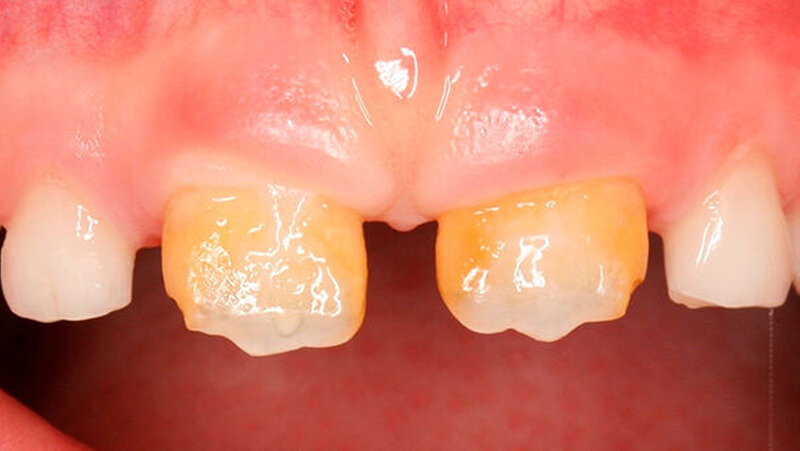

Das klinische Bild der MIH reicht von einem bis zu vier betroffenen Molaren, nur selten sind alle Zähne in ähnlicher Ausprägung geschädigt [Weerheijm et al., 2001]. Die bleibenden Frontzähne können ebenfalls betroffen sein, diese weisen allerdings in der Regel keinen Schmelzeinbruch auf und sind selten bis gar nicht überempfindlich [Weerheijm et al., 2001] (Abbildung 2).

Bisher wurde nicht beschrieben, dass die Frontzähne nur allein betroffen sein könnten. Meist wird - wenn die Frontzähne zusätzlich zu den Molaren betroffen sind - über mangelnde Ästhetik geklagt und die Kinder aufgrund ihres Aussehens gehänselt.

Bleichen und/oder Mikroabrasion können eine Verbesserung der Ästhetik bewirken, ein Ergebnis ist aber oft nur schwer vorherzusagen und gelegentlich wird sogar eine Kombination beider Verfahren notwendig. Die Mikroabrasion erscheint gelegentlich für die Behandlung milchig-weißer Defekte besser zu wirken als das Bleichen, wohingegen dieses für gelblich-braune Defekte eher geeignet zu sein scheint. Eine anschließende Versiegelung kann das Ergebnis optimieren.

Die Infiltration dieser Läsionen wurde ebenfalls diskutiert, zeigt aber ebenfalls bisher keine vorhersagbaren Ergebnisse.

In schwerwiegenden Fällen kann der Einsatz eines Komposits das beste Ergebnis erzielen (Abbildungen 2, 13 und 14)